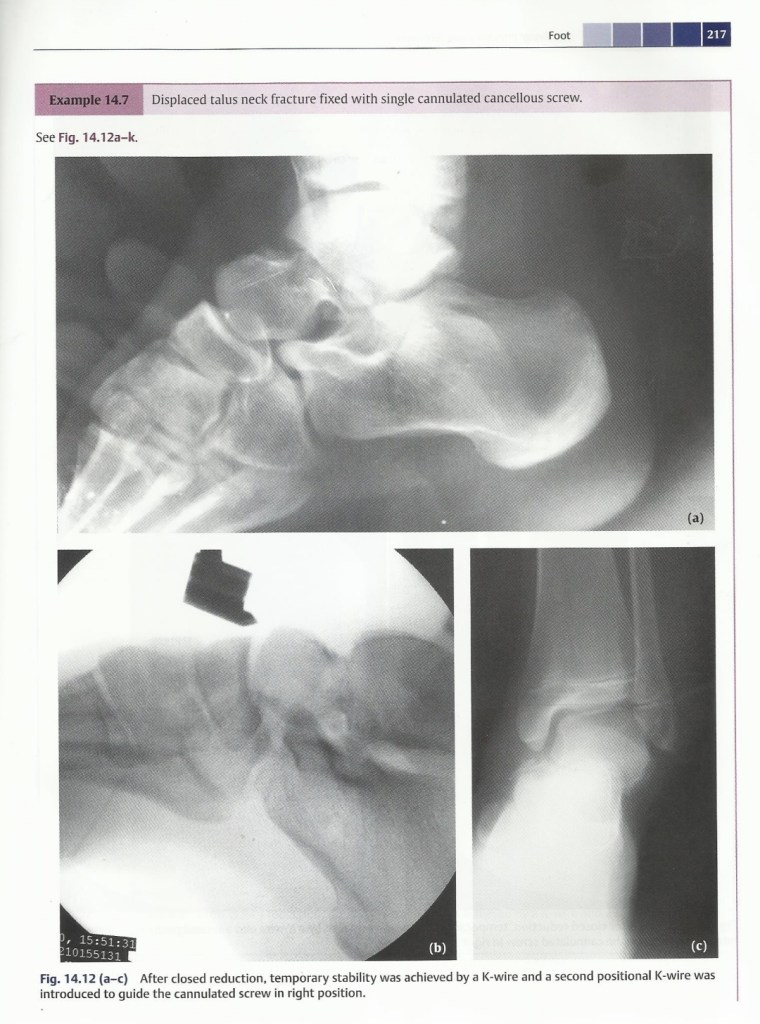

Talus fracture & Subtalar dislocation